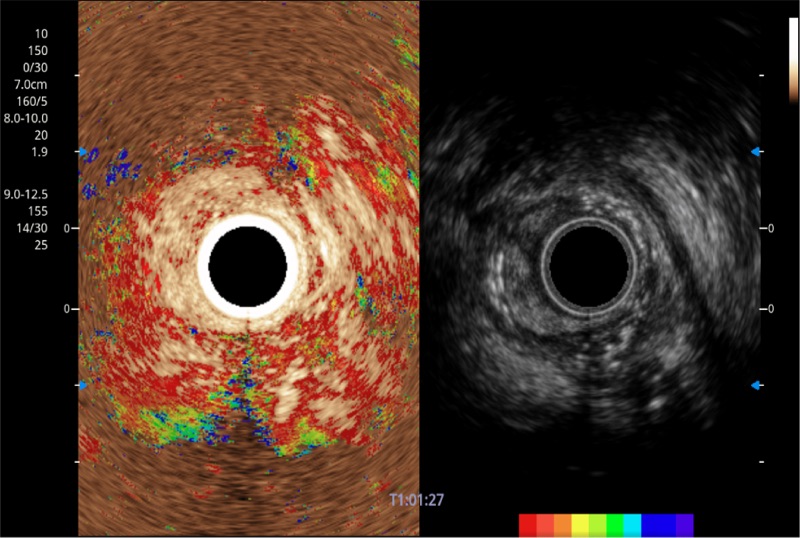

• 伪彩(Chroma)

可人为将灰阶图像转变成彩色的显示方式,增强人眼对于不同回声强度的敏感度,主观上增加了图像分辨率

• 弹性成像

位移矫正技术

不可靠区域自动剔除

弹性定量分析软件